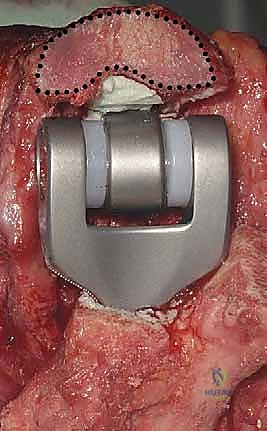

4. تركيب المفصل الصناعي التجريبي

قبل وضع المفصل النهائي، يتم وضع مفصل "تجريبي" لاختبار نطاق الحركة، واستقرار المفصل، وشد الأربطة. هذه الخطوة تضمن عدم وجود أي إعاقة للحركة بعد العملية.

5. تثبيت المفصل النهائي (الإسمنت العظمي)

يتم استخدام المفصل الصناعي النهائي، والذي يتكون غالباً من سبيكة معدنية عالية الجودة (مثل الكوبالت والكروم أو التيتانيوم) مع بطانة من البولي إيثيلين لضمان حركة سلسة. يتم تثبيت جذوع المفصل داخل العظام باستخدام "الإسمنت العظمي الطبي" (Bone Cement) الذي يضمن ثباتاً فورياً وقوياً، وهو أمر حاسم لمرضى هشاشة العظام.

6. ربط المفصل وإغلاق الجرح

بعد جفاف الإسمنت، يتم ربط جزئي المفصل (العضد والزند) معاً بمحور معدني (Linked Prosthesis)، مما يمنع خلع المفصل مستقبلاً. يعيد الدكتور هطيف بناء الأوتار (خاصة وتر العضلة الثلاثية) بدقة متناهية، ثم يتم إغلاق الجرح تجميلياً.